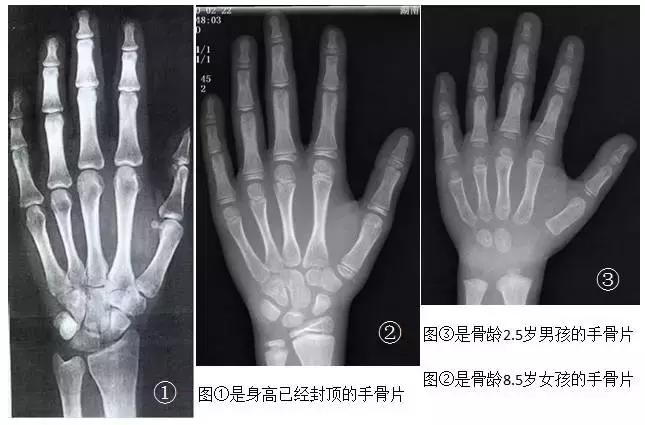

怎么测量呢?去医院找医生,拍摄手部的X光片,医生通过观察X光片来确定骨龄。一般男孩骨龄达到16岁,女孩骨龄达到14岁,骨骼生长板就接近闭合,长高希望就不大了。

生物年龄(骨龄)-生活年龄的差值在±1岁以内的称为发育正常。

生物年龄(骨龄)-生活年龄的差值>1岁的称为发育提前。

生物年龄(骨龄)-生活年龄的差值<1岁的称为发育落后。

如有必要,6岁以后可以每隔2-3年测量一次骨龄,了解孩子骨骼生长的状况和预测身高,测量结果不理想,应及早进行干预。